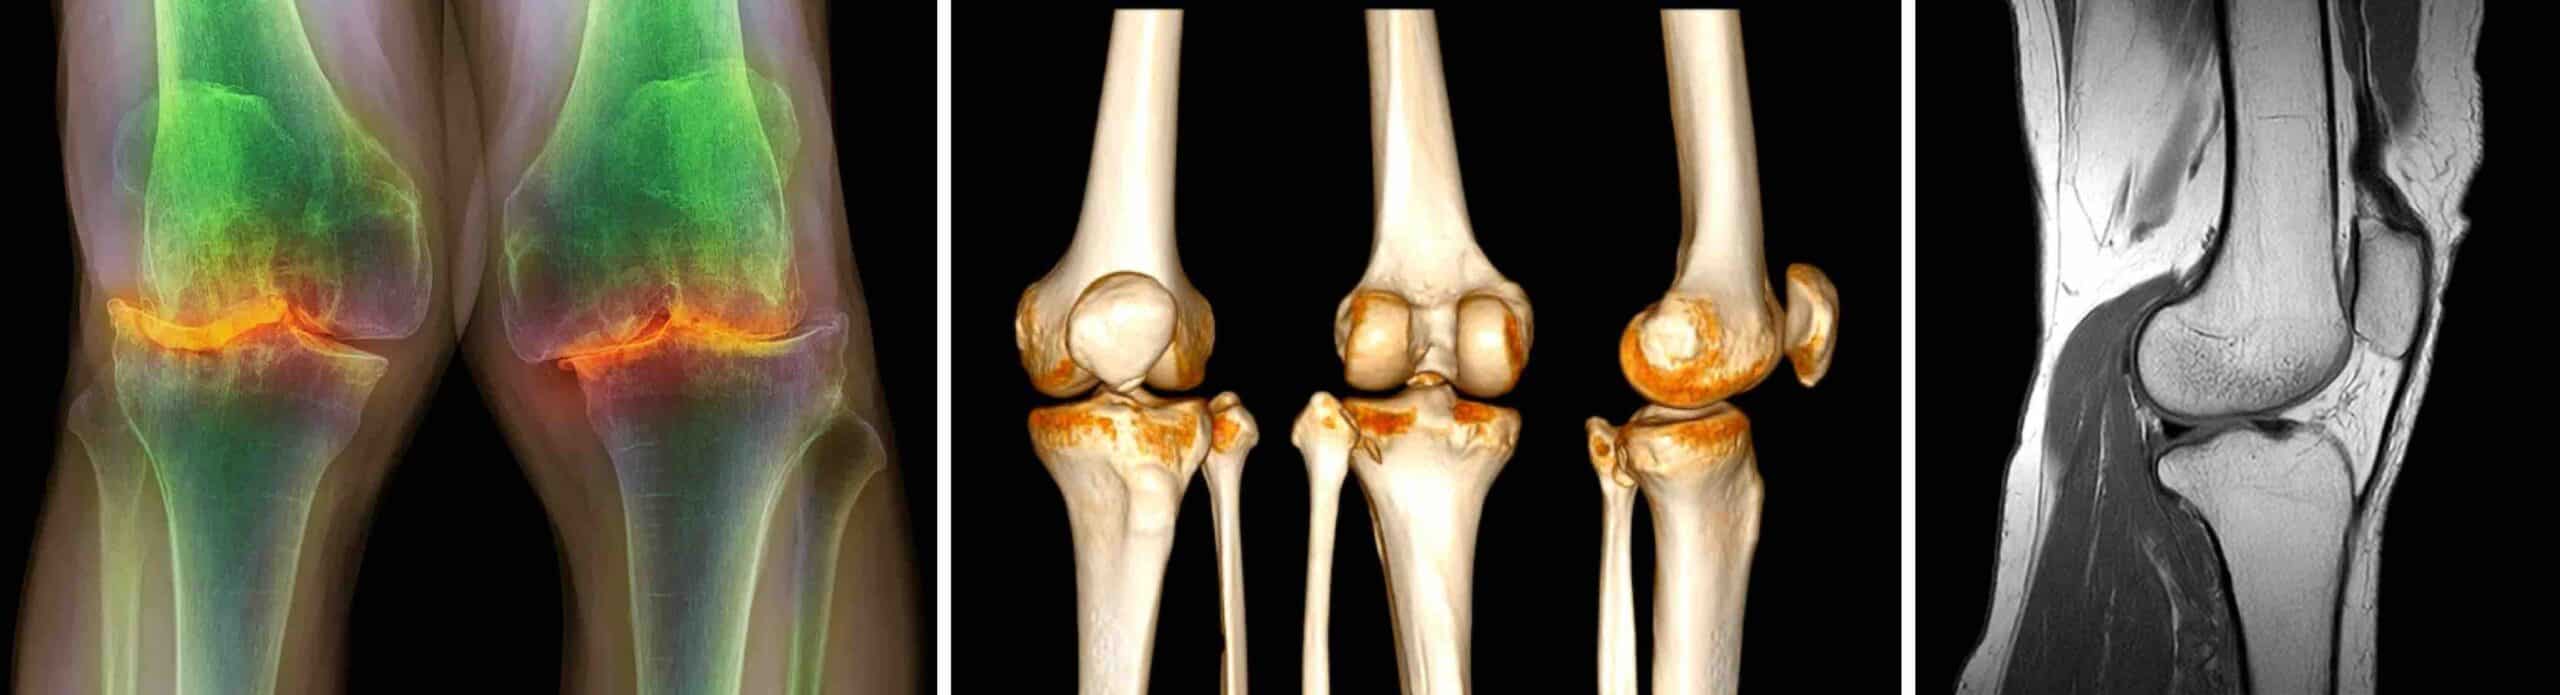

ARTROSE

Artrose é a doença que mais acomete o joelho. Ela é caracterizada pelo desgaste da cartilagem, principalmente em pessoas acima dos 50 anos. Quando a cartilagem que reveste os ossos dentro da articulação se desgasta, pode haver atrito ósseo entre o fêmur e a tíbia ( artrose femorotibial ) ou entre a patela e o fêmur ( artrose patelofemoral ). Osteófitos, geodos, cistos subcondrais e deformidades ósseas causados pela artrose intensificam a dor.

DIAGNÓSTICO

O diagnóstico de dor no joelho de origem óssea é feito pelo exame físico da articulação e por exames de imagem como RX, tomografia computadorizada, ressonância magnética e cintilografia óssea. Os exames de imagem identificam alterações ósseas, fraturas, tumores e degenerações articulares.